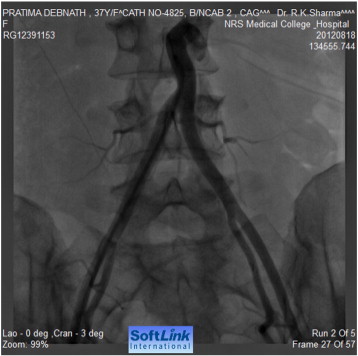

CT angiography showed agenesis of abdominal aorta from origins of renal arteries, abnormal branching of superior mesenteric artery forming vascular loop and reconstituting lower aorta, and large aneurismal dilatation of the distal part of the gastroduodenal artery (Fig. 1).

CT angiography showing agenesis of abdominal aorta, collaterals reconstituting ...

CT angiography showing agenesis of abdominal aorta, collaterals reconstituting the lower abdominal aorta and the aneurysm from gastroduodenal artery.